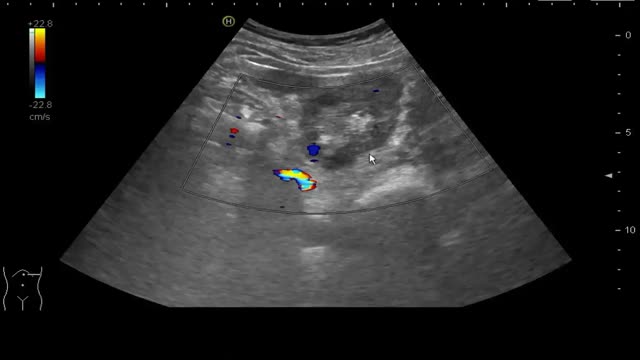

Ecográficamente las litiasis se observan como estructuras hiperecogénicas puntiformes o con forma de teja, con 2 artefactos ecográficos que apoyan el diagnóstico, la sombra acústica posterior y el artefacto centelleo con Doppler color (fig. 2 y video 3).

Se localizan en cualquiera de los cálices renales, en la pelvis renal, uréteres y vejiga. Son visibles con ecografía cuando son superiores a unos 4mm y son más fáciles de visualizar cuando se localizan en los calices o en la vejiga; y mucho más difíciles en el trayecto de los uréteres13.